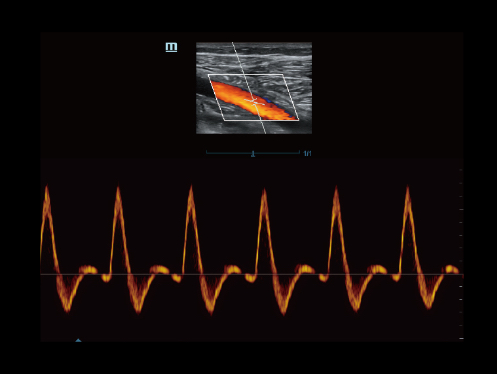

Echo Boost yang canggih

Terobosan beruntun Mindray untuk visualisasi gambar ultrasound terbaik.